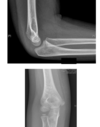

describe x ray in 9 year old what are the immediate management priorities? complications

* elbow dislocation posterior and laterally * small bony fragment on epiphysis - relevant as medial and 9 years old **management** analgesia ?neurovascular compromise any other injuries or NAI **Complications** neurovascular compromise difficult reduction in bone fragment in the way malunion,non union, chronic pain poor function

38

important findings

closed supracondylar fracture fat pad sign, soft tissue swelling

40

7 year old girl with pain. key features?

anterior and posterior fat pads visible cortical disruption of posterior humeral surface at level of olecranon fossa non displaced supracondylar fracture